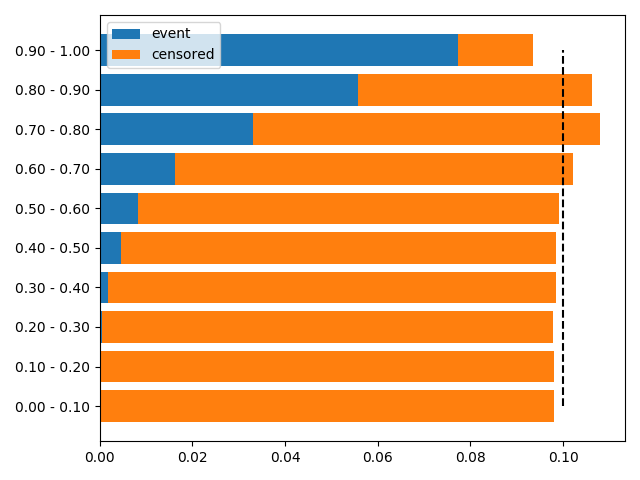

In total, our survival dataset contains 17,230 images with prostate tissue, of which 60 images that either contain little to no tissue or are of poor quality (e.g. artifacts in the image) are omitted. Additionally, 3,624 patients with unknown relapse time or censoring status are excluded. 709 patients fall under the filtering criterion described in \sectionrefsec:dataset. Since multiple exclusion criteria may apply to one patient, 14,479 patients remain in the final survival dataset. The dataset distribution is shown in \figurereffig:apd_data_distribution for the training and validation sets. 90% of uncensored events occur prior to 7 years, 44% prior to 2 years.

The d-calibration for eCaReNet is shown in \figurereffig:apd_result_dcal. The distribution’s uniformity has been confirmed with a chi-square test. The AUC of eCaReNet can also be evaluated over time, as shown in \figurereffig:auc_time.

fig:apd_result_dcal

Appendix D D-calibration

In a d-calibrated model, the survival functions per patient can be interpreted as probability of relapse over time. If a survival curve shows 90% survival probability, the patient can trust that only 10% of patients with the same diagnosis experience a relapse at that time point. This also means that 10% of patients should experience their event when the survival probability is between 90 and 100%. Since the same holds for all other intervals (0-10, 10-20, …), the expected number of events is compared to the true number of events and a chi-square test is used to measure this. Censored patients need to be treated differently from uncensored patients, because their true event time is not known. For details, see (Haider et al., 2020).